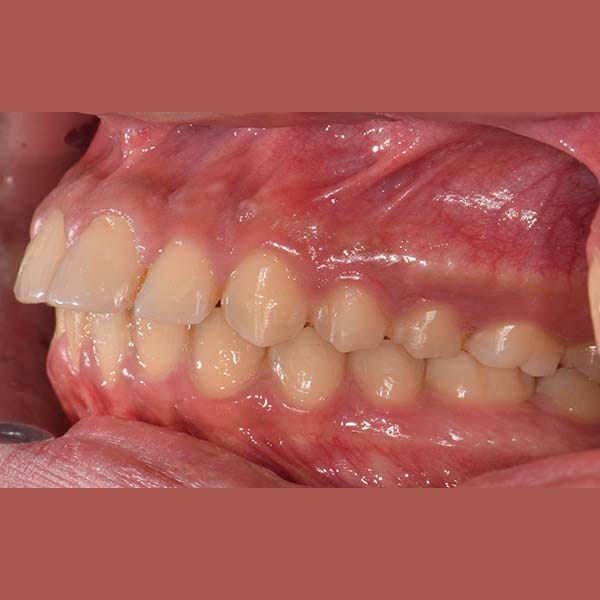

BEFORE

عانى هذا الشاب اليافع من بروز في الأسنان الأمامية العلوية بسبب تراجع الفك السفلي. أثرت هذه المشكلة على قدرته على قطع الطعام بشكل جيد، بالإضافة إلى شعوره بالخجل من الابتسام أمام أصدقائه في المدرسة.